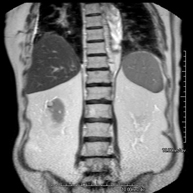

- Abdomen MRI

This non-invasive diagnostic procedure uses an electromagnetic field and radio waves (from a transmitter and receiver) to acquire high-definition anatomical images of the abdomen. It is a radiation-free procedure. This examination includes the liver, pancreas, spleen, bile duct, gallbladder, adrenal glands, kidneys, abdominal aorta, inferior vena cava, stomach, duodenum, etc. Sometimes paramagnetic contrast (gadolinium) must be used to complete the study.